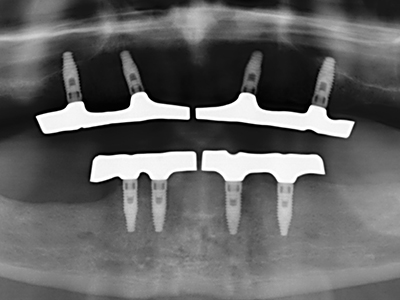

Пиезохирургията има допълнителни предимства при събиране на костни блокове. В допълнение към високата прецизност при остеотомията, описана по-горе, употребата на фините режещи накрайници значително намаляват загубата на материал. Голяма загуба на материал по време на събиране може да се очаква с дебелите накрайници, особено при употреба на борери Линдеман (Lakshmiganthan, Gokulanathan et al. 2012). Базалното разделяне, което е необходимо, особено за присадка на блок при ретромолар, е улеснено от специално създадени правоъгълни триони. В резултат на това, пиезохирургията е разглеждана като прецизна, улеснена и безопасна процедура за събиране на костни блокове в ретромоларното пространство (Happe 2007) (Фиг. 1-12).

Индикация: Костно разделяне/ шиниране?

Костната тъкан е не само минерализирана структура, тя съдържа и съществено количество колагенови влакна. Това означава, че тя има не само добра компресивна сила, но и известна степен на гъвкавост, която може да се възприеме като предимство при извършване на костна аугментация. В класическата процедура по разширяване чрез костно разделяне, атрофиралият алвеоларен гребен е разделен надлъжно и внимателно разширен след достигане на подходящата остеотомна дълбочина (Фиг. 13-16), в идеалния случай без допълнително отстраняване на периостеума (Brugnami, Caiazzo et al. 2014, Stricker, Fleiner et al. 2014). Системите с винт и пластини с увеличаване на разстоянието при разширяване са доказали ефективността си при разделяне на двете костни ламели, оставайки под прага на фрактурите. В общи линии, оставащата ширина на костта от поне 3–4 mm е задължителна (Chiapasco, Zaniboni et al. 2006), за да се гарантира добра гъвкавост и достатъчно костно покритие за бъдещото поставяне на импланти. Ако е необходимо, вертикалната остеотомия на едната или двете страни може да подобри гъвкавостта. Комбинацията с допълнителни техники за аугментация, особено в букалната страна, е описана като алтернатива на класическата техника.

Процедурата по разделяне е атравматична и няма голяма загуба на пространство, използвайки пиезотриони, и няма значителна разлика между импланти в разделени челюсти и импланти в алвеоларния гребен без костен дефицит (Chiapasco, Zaniboni et al. 2006, Danza, Guidi et al. 2009). Въпреки това, важно е да има достатъчно и продължително охлаждане, особено при ограничено и дълбоко разделяне, за да се избегне термичен стрес в апикално-остеотомните зони.